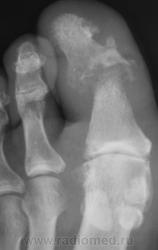

Пациент направлен на рентгенографию первого пальца.

и при таком лизисе..нет клиники?

Клиника есть, клиника остеомиелита.

мне увиделось что мягкие ткани не сильно отреагировали..